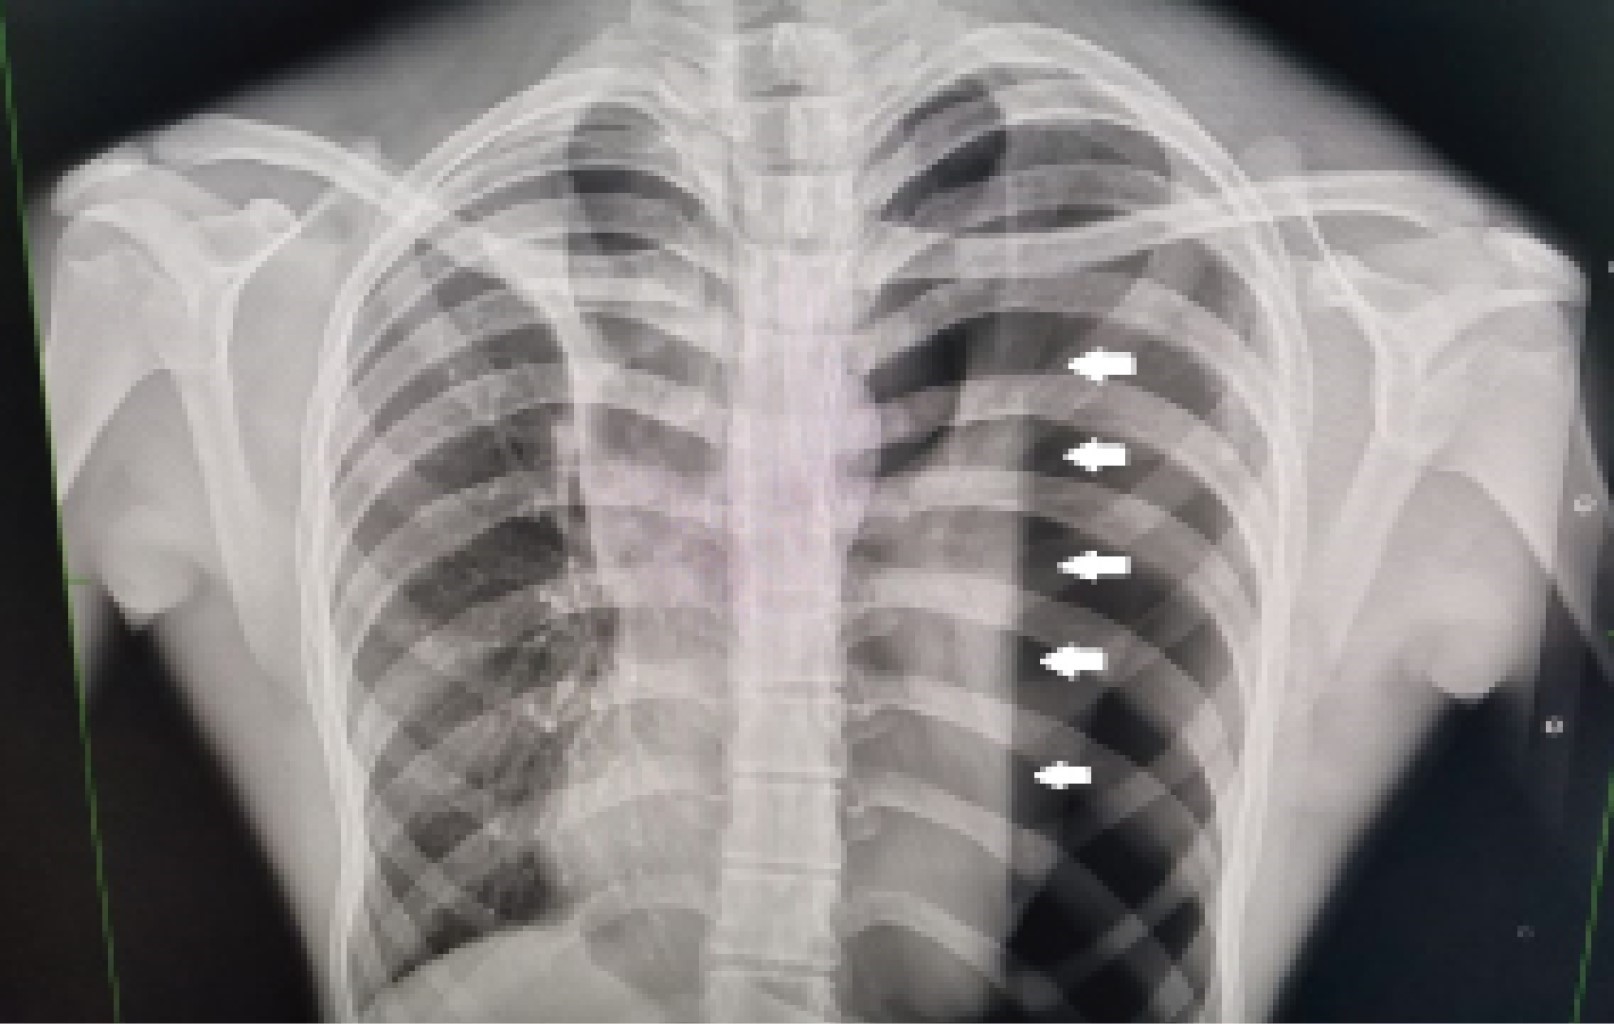

Three weeks later, he came to the emergency department referring a two-day evolution of pain in the left hemithorax, of sudden onset, transfixing, as well as dyspnea at rest; the physical examination revealed hypoventilation of the left hemithorax and hyper resonance to percussion. The X-ray showed recurrent pneumothorax (Figure 1) and an endo pleural probe was placed. Adequate pulmonary expansion was seen on X-ray (Figure 2). Seven days later the patient underwent a seal pleural probe test, presenting dyspnea and chest pain. A control X-ray showed recurrent left pneumothorax (Figure 3), so a CT scan was requested, showing persistent pneumothorax, and left apical bulla, so a surgical protocol for thoracoscopy was initiated.

Figure 3